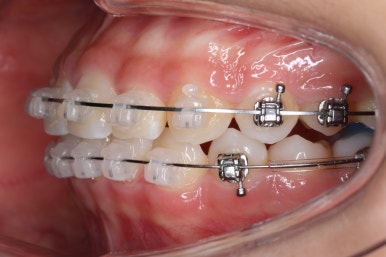

윗니에도 이제 장치를 모두 붙였습니다. 아래쪽은 어느 정도 가지런해지고 나면 부족한 자리를 만들어주기 시작합니다.

부산치아교정잘하는곳 키다리아저씨치과에서 이번 환자분에 사용한 장치는 데이몬 클리어라고 하는 세라믹 자가결찰 장치입니다. 세라믹 자가결찰 장치 중에서 철사를 잡아주는 CAP 부위까지 세라믹으로 되어있어 가장 심미적인 장치라고 볼 수 있습니다.

예상한대로 자리만 충분히 마련해주니 그동안 나오지 못하고 막혀있던 치아가 슬그머니 고개를 내밀고 있습니다.

좀 더 기다렸다가 좀 더 올라오면 장치를 부착해서 정리해주기만 하면 되겠습니다.

부산치아교정잘하는곳 키다리아저씨치과에서는 치아가 올라오자마자 장치를 부착하여 가지런하게 해줍니다. 이제 어느 정도 큰 그림은 그려졌다고 보시면 되겠습니다.